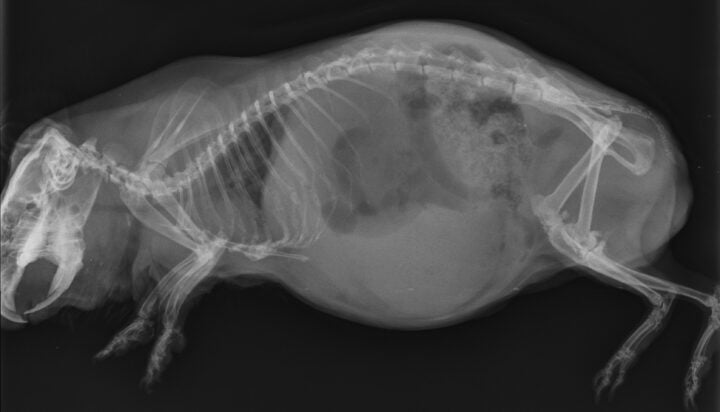

Often, clinical signs are missed, and the diagnosis in guinea pigs is made during post-mortem examination (DeCubellis and Graham, 2013). However, when present, clinical signs can range from anorexia, lethargy, tachypnoea, an absence of faecal production, cyanosis and cardiovascular shock to sudden death (DeCubellis and Graham, 2013; Edis, 2019). Patients can be presented obtunded, with palpable gastric tympany and hypothermia (Mitchell et al., 2010). It is important to distinguish this condition from bloat – another common condition in which guinea pigs present with gastric tympany.

GDV is an emergency presentation that must be identified quickly. The gaseous distension of the stomach causes it to twist on its axis at the mesentery, resulting in compression of the gastric vessels and secondary ischaemia (Edis, 2019). Fermentation of ingesta contributes to further gaseous distension in the stomach that cannot escape as the gastric outflow is also obstructed due to the twisting of the stomach.

Diagnosis is often by radiography, which should be performed following administration of analgesia and sedation if required. Radiographs show severe gaseous distension of the stomach, often taking up 50 percent of the abdominal cavity (Huynh and Pignon, 2013). In some cases, the bowel can be visualised cranial to the stomach (Mitchell et al., 2010) (Figure 5). It is important to note that the classic “double bubble” seen in cases of GDV in canine patients is not always seen radiographically, and diagnosis of GDV in guinea pigs should not be ruled out based on the absence of this sign.